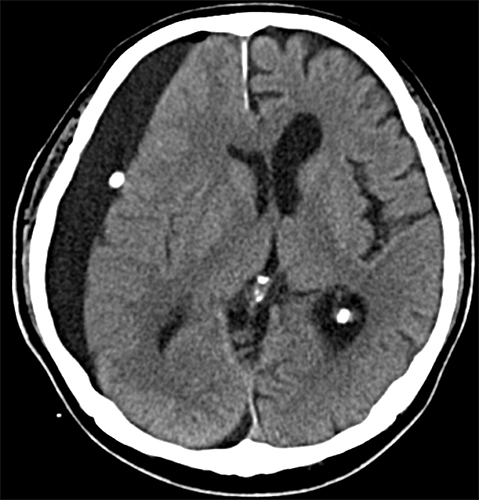

경막하 출혈의 진단은 환자의 신체검사와 함께 여러 가지 검사방법을 통해 이루어집니다.

- CT 또는 MRI 스캔 : 출혈량과 위치를 확인하기 위해 실시됩니다.

- 관찰 치료 : 환자의 상태가 양호하고 출혈량이 적은 경우, 정기적으로 CT 검사를 통해 출혈량을 모니터링하며 경과를 지켜보는 방법도 사용됩니다.